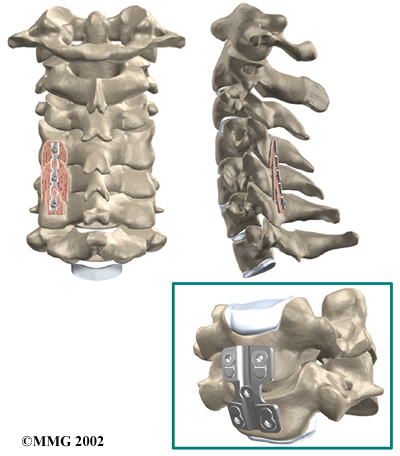

Cervical Fusion

A fusion surgery joins two or more bones into one solid bone. The purpose for doing spinal fusion is to increase the space between the vertebrae and to keep the sore joint from moving. This is usually done by placing a small block of bone graft in the space where a disc was removed. Opening up more space enlarges the neural foramen, takes pressure off the nerve roots, and eases tension on the facet joints. Cervical fusion is used to treat neck problems such as cervical radiculopathy, disc herniations, fractures, and spinal instability. There are two main types of fusion for neck problems.

The bone graft needs time to heal in order for the fusion to succeed. This requires the neck to be held still. After cervical fusion surgery, patients usually have to wear a special neck brace for several months. These neck braces are often bulky and restrictive. Recently, surgeons have begun using metal plates and screws (often referred to as instrumentation) to lock the bones in place. The instrumentation is fastened to the vertebrae, where it holds the bones still while the graft heals.

Locking the Bones in Place